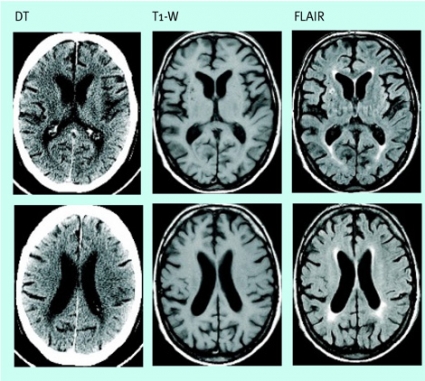

Intracerebrala hematom

Hemorragi är orsaken till stroke hos bara cirka 15 procent av patienterna, men hemorragi är en viktig differentialdiagnos, som enkelt påvisas eller utesluts med DT i rutinfallet. MR har mycket stor känslighet för blödningar (Figur 1), och ett diagnostiskt program för akut stroke kan mycket väl drivas enbart med MR, förutsatt att sekvenser känsliga för hemoglobinprodukternas paramagnetiska egenskaper ingår: tex T2*-gradientekobilder [1, 2] eller de mycket susceptibilitetskänsliga (dvs känsliga för vävnadens magnetiska egenskaper) snabba ekoplanära gradientekosekvenser som används för perfusionsviktad MR.

Datortomografi har större känslighet för dessa förändringar än vad som allmänt antogs för något decennium sedan, om man ser till att upplösningen av låga kontraster är god. DT kan ofta påvisa infarktförändringar med låg attenuering efter 1–1,5 timmar, i sällsynta fall redan efter 50–60 minuter. Konventionell MR-teknik (tex T2-viktade bilder) har bara marginellt större känslighet för tidiga infarktförändringar, med en fördel framför DT endast vid förändringar i bakre skallgropen [3].

Diffusionsviktade MR-bilder (DWI), som framför allt avspeglar protonernas rörlighet i det extracellulära vattnet, har däremot mycket hög känslighet för det cytotoxiska ödemet. Cellsvullnaden orsakar en sekundär inskränkning av extracellulära rummet vid tidiga infarkter, och DWI kan påvisa sådana förändringar redan efter minuter. Sensitiviteten respektive specificiteten med DWI de första 6 timmarna efter infarktinsjuknandet anses vara i storleksordningen 95 procent respektive nära 100 procent [4], och känsligheten även för små lakunära infarkter är vida överlägsen känsligheten med DT.

DWI-bilderna ger således hög kontrast och lämpar sig väl för att påvisa patologiska förändringar (Figur 3). Diffusionen låter sig också beräknas i absoluta tal som »apparent diffusion coefficient« (ADC). Sådana bearbetningar eliminerar effekterna av tex förhöjd T2-signal, som annars kan leda till misstolkningar, och gör att man kan skilja cytotoxiskt ödem från vasogent.

Man kan inte visualisera den småkärlssjukdom med väggförtjockning av små perforerande artärer och arteriolier som anses vara orsaken till lakunära infarkter. Kliniska neurologiska fynd som vid ett lakunärt syndrom (tex rent motoriskt eller sensoriskt bortfall) kan ge stark misstanke om en sådan orsak till akut stroke. MR med diffusionsviktade bilder kan oftast påvisa lakuner eller avgöra om de är färska eller nytillkomna. Med DT, eller konventionella MR-bilder, är denna typ av infarkter ofta svåra att avgränsa från de mer diffusa vitsubstansförändringar som småkärlssjukdom ofta ger upphov till (Figur 8) och från vida men normala perivaskulära rum.